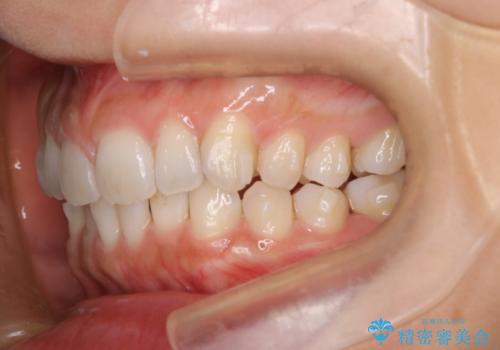

【インビザライン】前歯のねじれを治したい

- 前歯のガタガタを主訴に来院されました。

叢生の量は軽度でしたが臼歯の遠心移動を行い、インビザラインにて治療をしました。

叢生の改善に必要なスペースは遠心移動やIPRで作ることが可能です。今回は遠心移動をメインにスペースを作って叢生の改善を行いました。